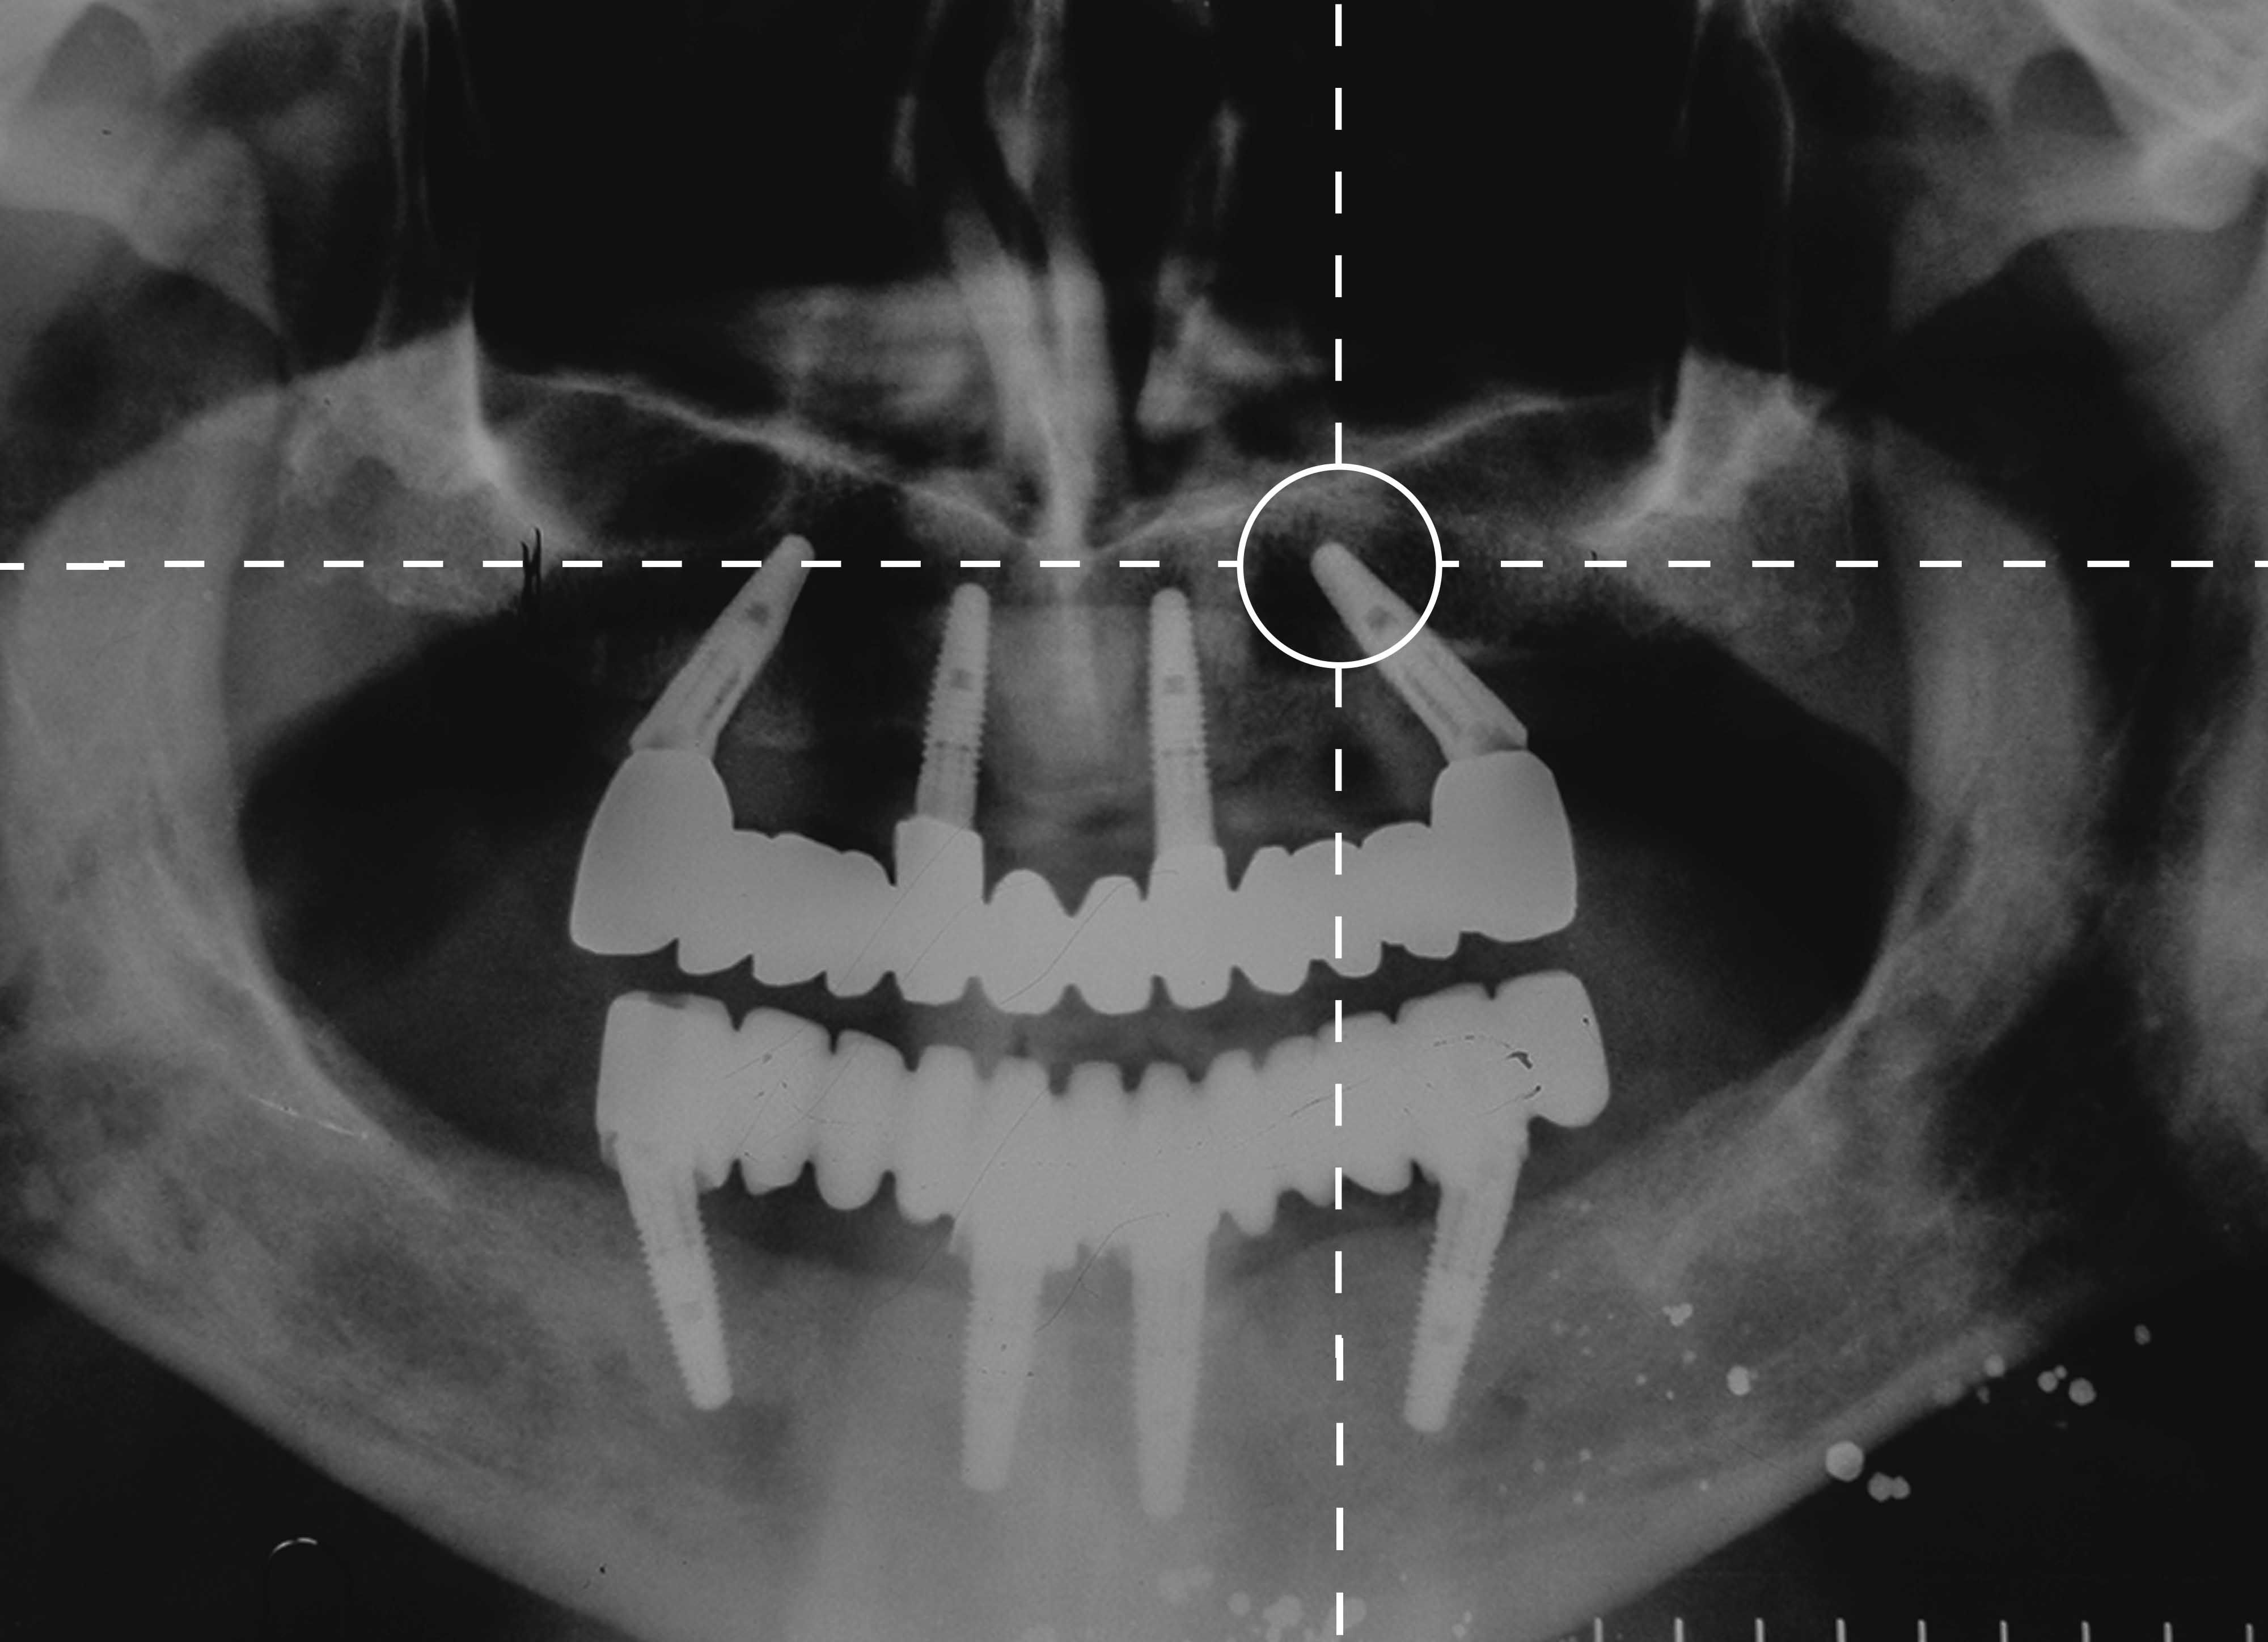

La periodoncia es una disciplina de la Odontología que se encarga del tratamiento de las enfermedades periodontales. Las más frecuentes son las gingivitis, que es la inflamación y sangrado de encías; y la periodontitis, pérdida de hueso, ligamento periodontal y cemento.

Su no tratamiento puede conllevar a la pérdida de la pieza dental.

En Clínica Dental Aizcorbe realizamos tanto tratamientos quirúrgicos como conservadores de enfermedades periodontales.